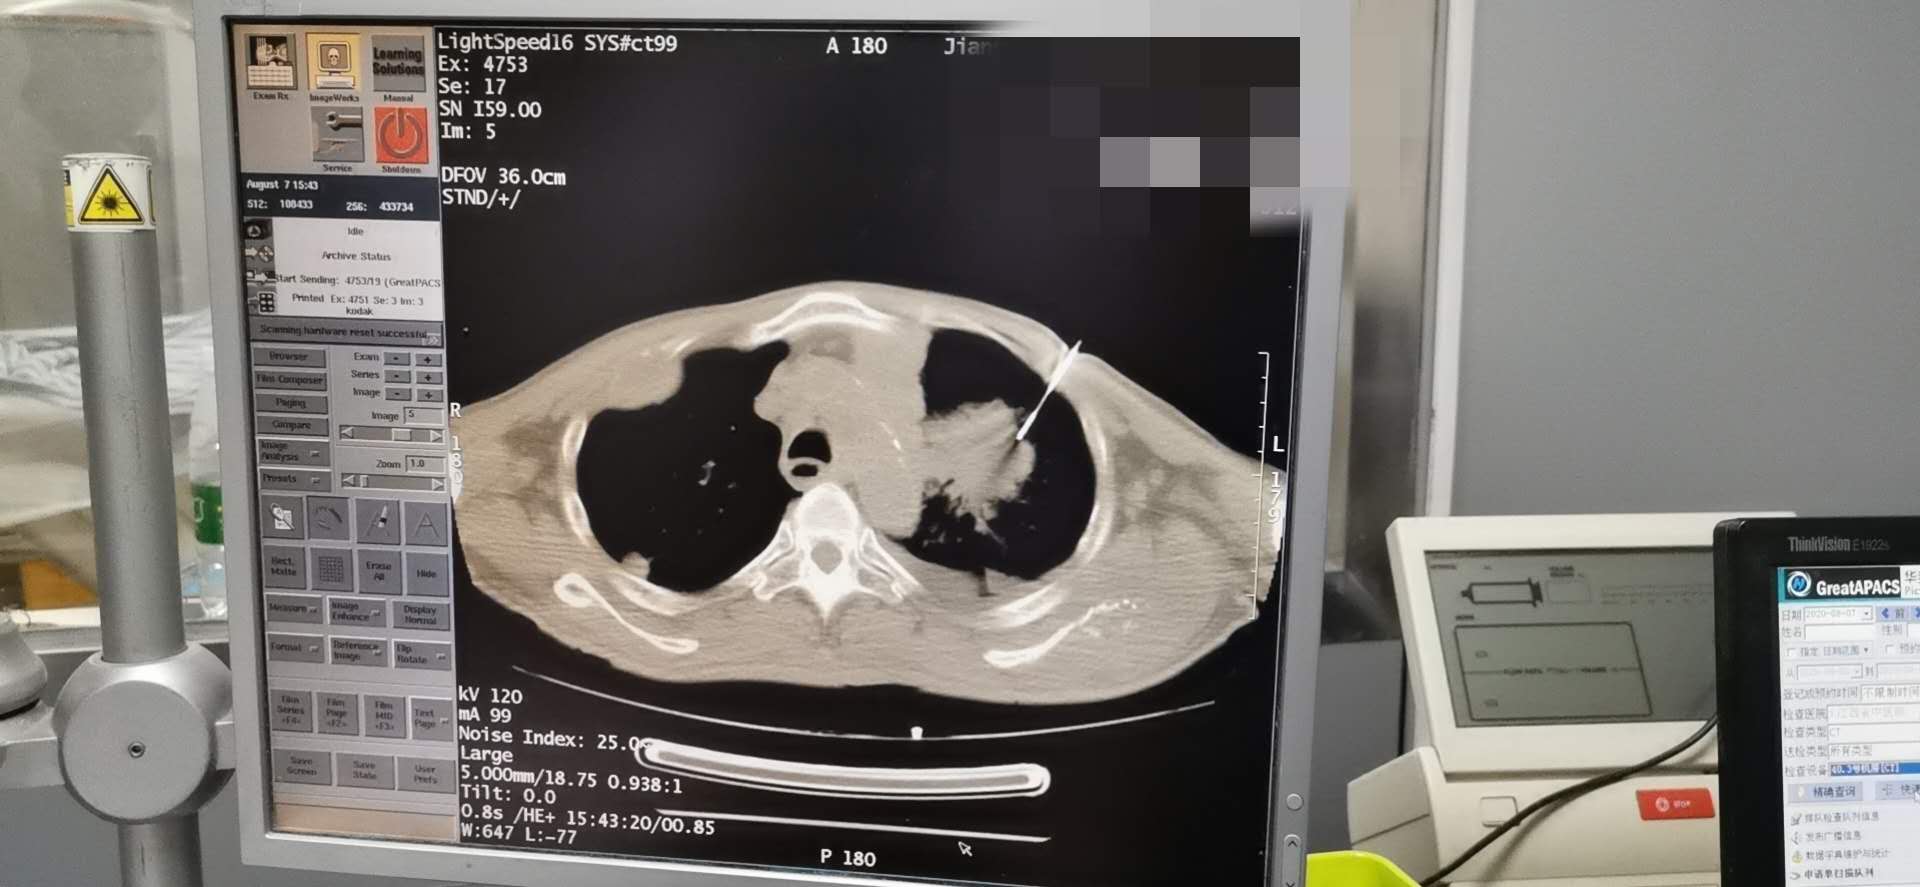

完成肺穿刺术一例

发布时间:2020-08-13点击次数:6232次